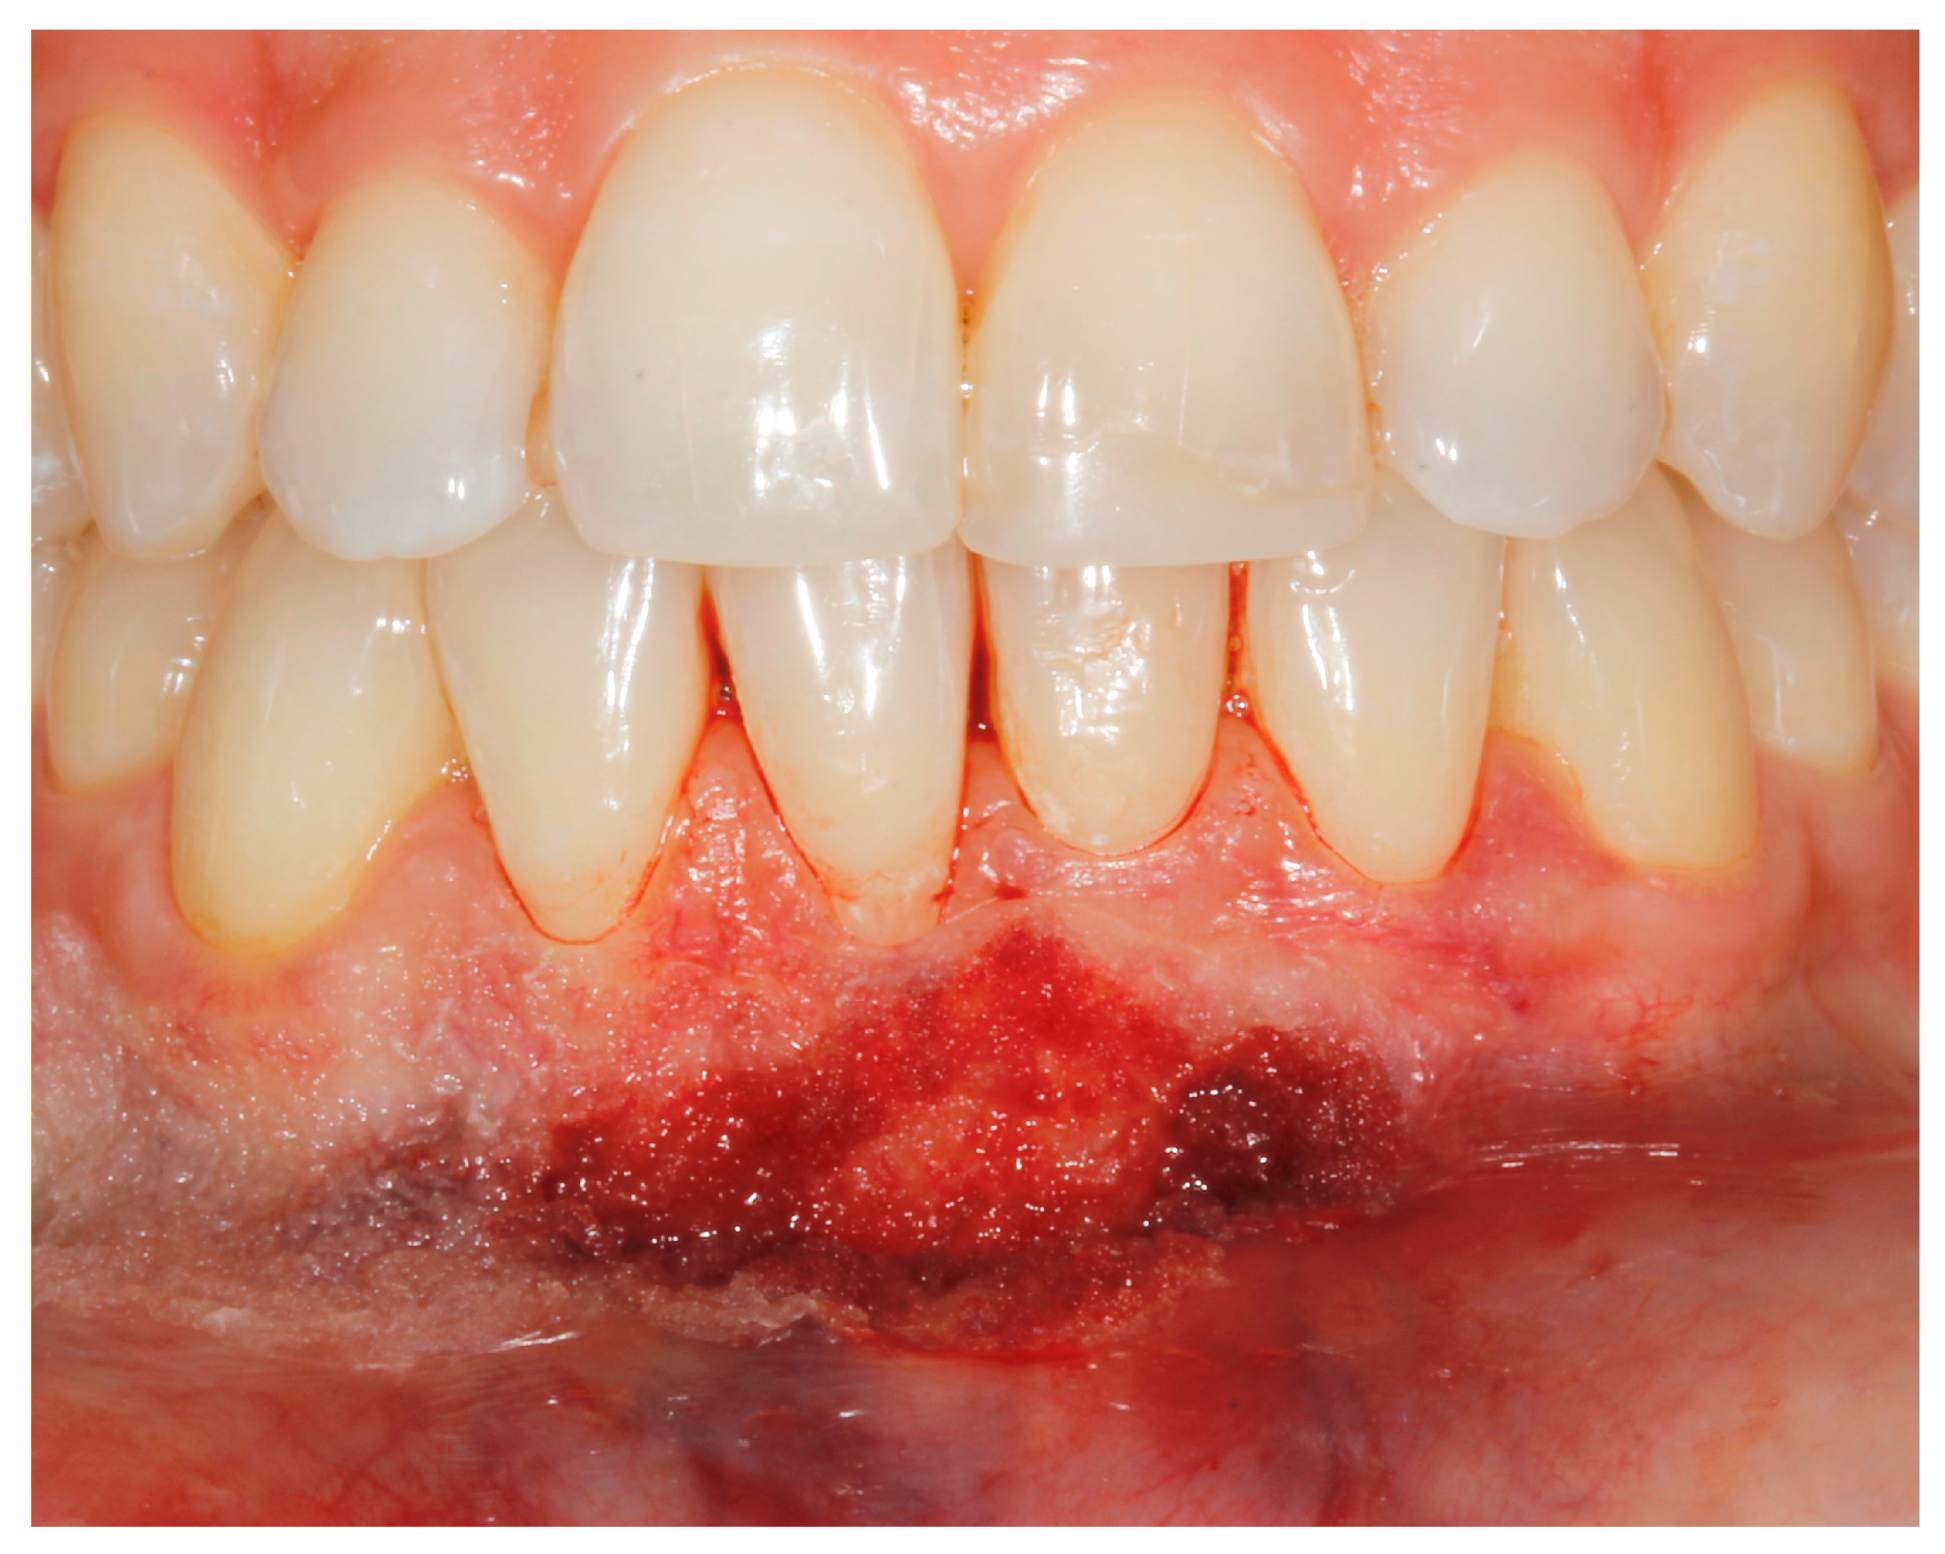

- (a)

- deep partial thickness incision (blade parallel to the periosteum) made at the level of the external insertion of the frenulum;

- (b)

- elimination of superficial mucous tissue and muscle of the frenulum;

- (c)

- a series of detached points with periosteal anchorage for the apical positioning of the lining mucosa of the lip and the second intention healing of the exposed periosteum.